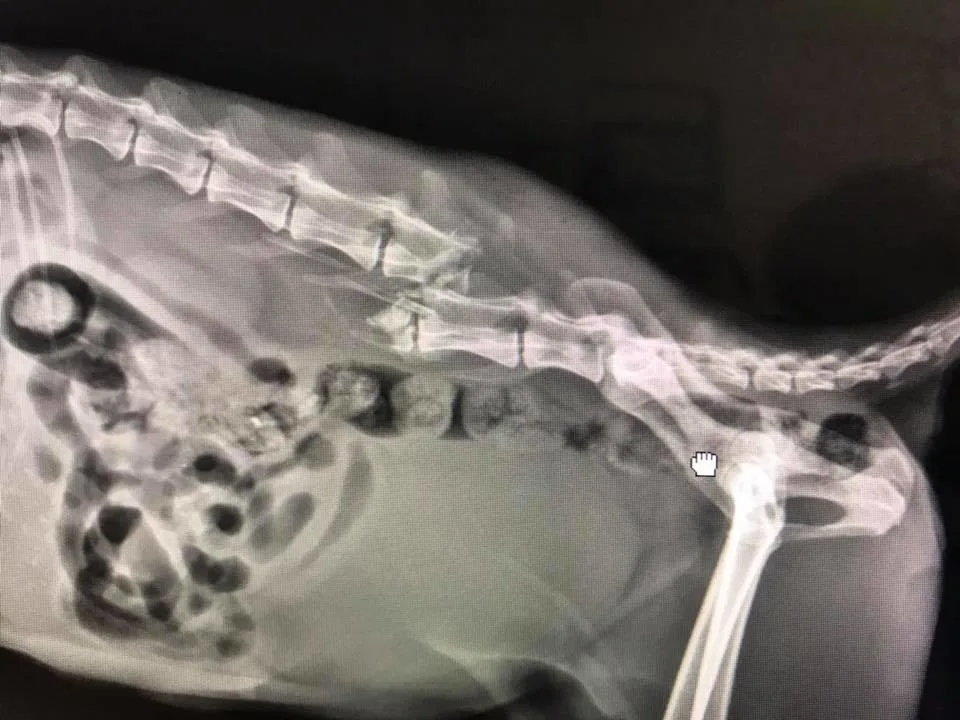

Her spine had been broken long ago, snapped so badly it no longer carried her strength.

She could not stand.

She could not walk.

Her spine was beyond repair.

It had been broken for far too long.

Her body had been surviving on will alone.